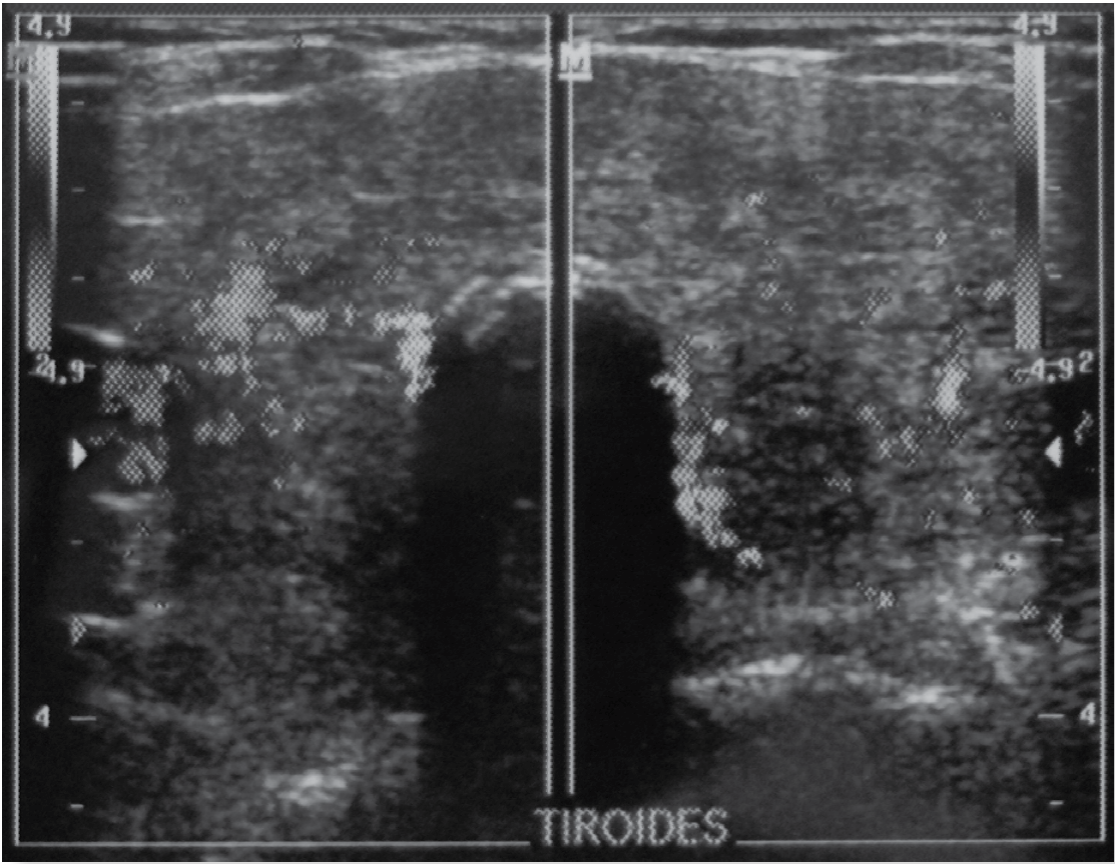

El perfil tiroideo (Tabla 1) documentó elevación de la forma libre de triyodotironina (T3) y tiroxina (T4); además de un incremento en la captación de T3 y disminución de la hormona estimulante de la tiroides (TSH). El ultrasonido reveló un aumento global en las dimensiones de la glándula tiroides con parénquima heterogéneo a expensas de múltiples nodulos hipoecogénicos e isoecogénicos mal definidos (Figuras 4 y 5); por lo tanto, se consideró que la tormenta tiroidea estuvo asociada al diagnóstico de bocio multinodular tóxico.

Foto: Autores

Figura 5 Ultrasonido tiroideo en escala de grises que muestra un corte transversal de los lóbulos tiroideos. Se observa aumento en sus dimensiones, bordes irregulares y parénquima heterogéneo a expensas de múltiples nodulos hipoecogénicos e isoecogénicos mal definidos.